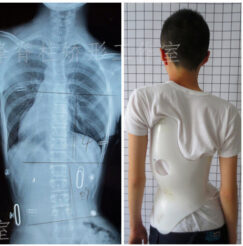

أهمية متابعة صور الأشعة أثناء ارتداء حزام اعوجاج العمود الفقري عند المراهقين

الدراسات الحديثة أوضحت أن الالتزام بارتداء الحزام وحده لا يكفي. بل إن إجراء صور الأشعة أثناء ارتداء الحزام بشكل دوري يعد عاملًا أساسيًا لنجاح العلاج، لأنه يسمح للطبيب بمراجعة فعالية الحزام وإجراء التعديلات اللازمة في الوقت المناسب.

الحزام الطبي يعمل على تقليل و تثبيت الانحناء أثناء النمو. لكن درجة فعاليته تعتمد على:

مدى ملاءمة الحزام للشكل الحالي للعمود الفقري.

قدرة الحزام على تصحيح الانحناء أثناء ارتدائه.

التعديلات التي قد يحتاجها الحزام مع نمو الطفل أو تغير شكل العمود الفقري.

صور الأشعة داخل الحزام تساعد الطبيب على:

التأكد من أن الانحناء يُصحح بشكل كافٍ أثناء ارتداء الحزام.

تعديل الحزام أو صناعته من جديد إذا لزم الأمر.

التنبؤ باحتمالية نجاح العلاج وتجنب فشل الحزام لاحقًا.